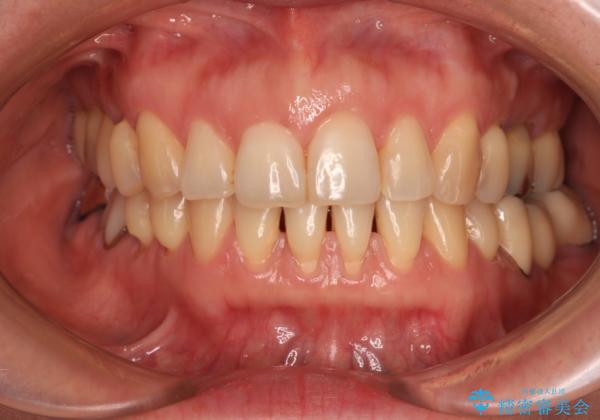

正中のズレと飛び出した前歯を改善 メタルブラケットでの抜歯矯正

- 飛び出した上顎前歯と正中のズレを気にして来院された患者様です。

上顎正中が右側にずれていたので、むし歯が酷く抜歯が必要な左側臼歯を抜歯して正中を改善することとしました。

左下には新しいセラミックのブリッジが装着されていたため、ブリッジを壊さずに改善できるところまで咬み合わせを改善していくこととしました。